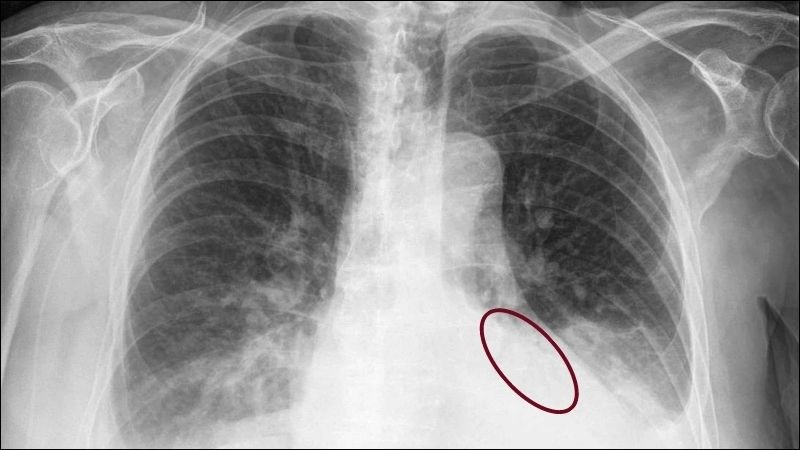

tràn dịch màng phổi Minh họa hình chụp X-quang của một ca tràn dịch màng phổi

• Chụp X-quang ngực: tổng quan tình trạng và chẩn đoán số lượng dịch tích tụ.